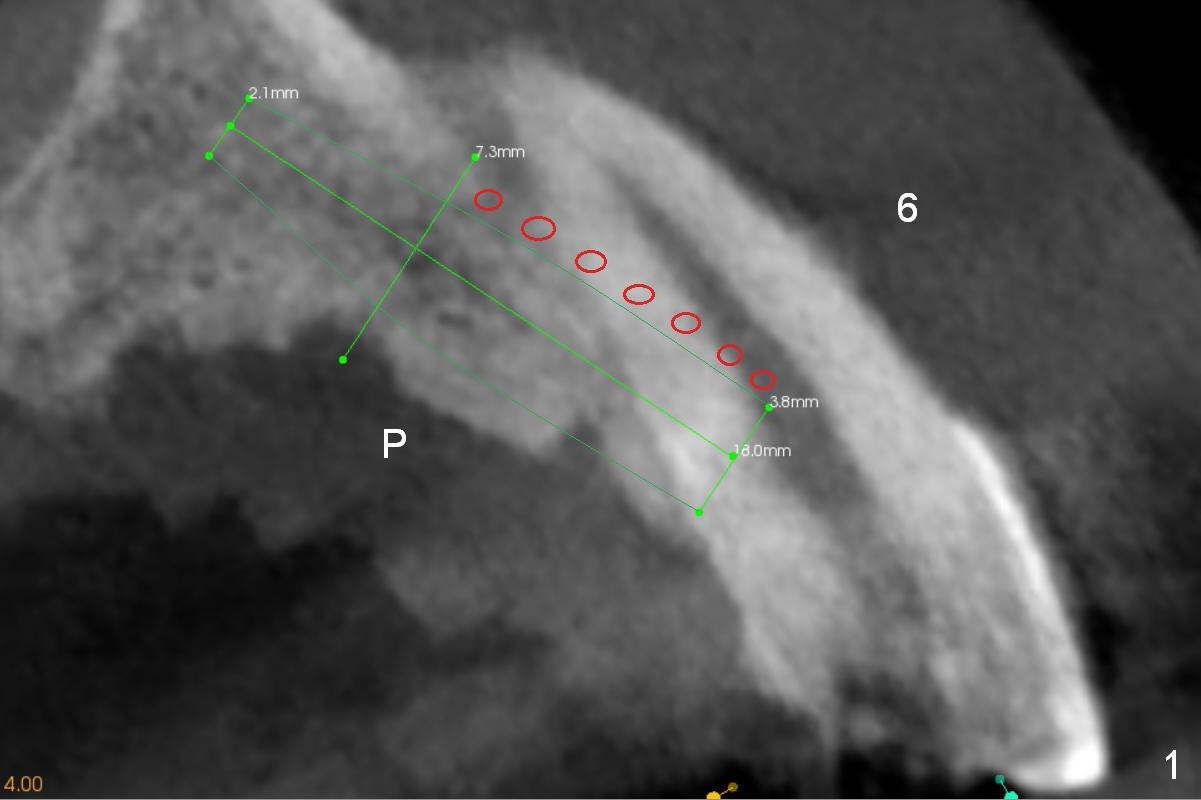

Alginate impression will most likely dislodge #11-15 loose FPD. Start osteotomy at #11 and 15 first (Fig.6, 10) and use the teeth #9 and 10 as trajectory reference. Prepare PRF (Fig.10 white curved line) and Magic Lifter for #15.

The bone width at #9 is narrow (Fig.3, as compared to Fig.2 for #8). Prepare SM (straight) and Tatum (angled) 1-piece implants. Try to place a 2-piece implant at #10 if possible (Fig.5, compare to Fig.4) so that FPDs and crowns can be converted to hybrid denture in the future.